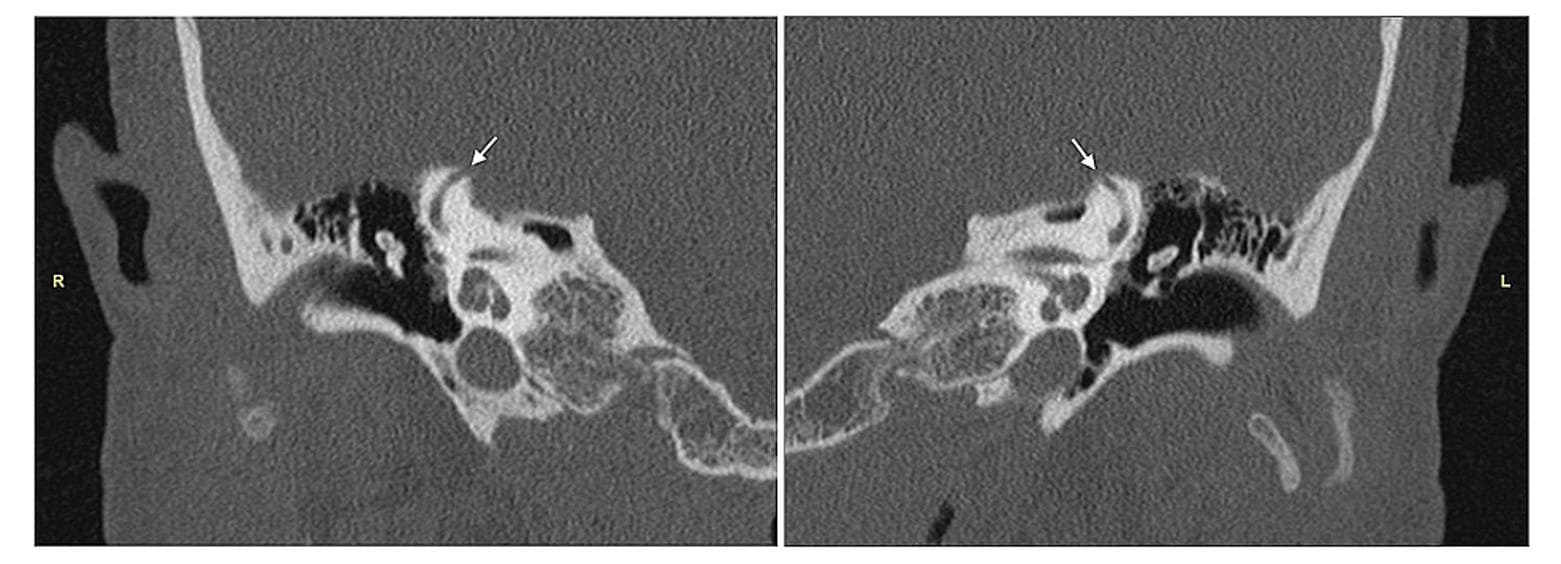

Superior Semicircular Canal Dehiscence (SSCD) is a condition characterized by thinning or opening of the bone at the top of the superior semicircular canal in the inner ear.

Superior Semicircular Canal Dehiscence (SSCD) is a condition characterized by thinning or an opening in the bony layer above the superior semicircular canal in the inner ear. This abnormality can affect hearing and balance systems.